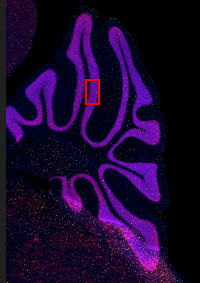

20배율로 획득한 40µm의 생쥐 뇌 시상 절편의 확장 초점 이미지(EFI).

X-Cite NOVEM LED를 사용하여 획득한 파란색(DAPI) 및 빨간색(NeuN, 뉴런). 노란색: VS-SILA 광학 절단 장치를 사용하여 획득한 Iba1(미세아교세포).

샘플은 오스트리아 파라셀서스 의과대학(Paracelsus Medical University), Spinal Cord Injury and Tissue Regeneration Center Salzburg의 Institute of Experimental Neuroregeneration에서 제공했습니다.